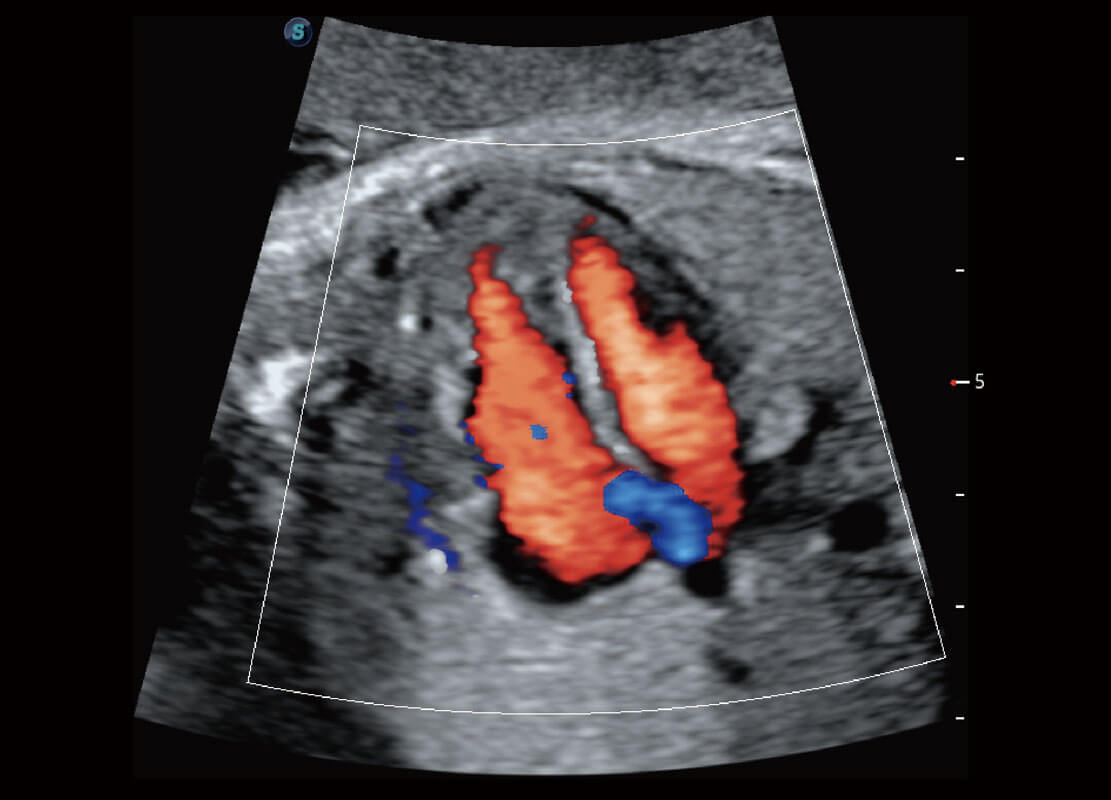

• 胎儿体循环

• 光影成像-孕囊